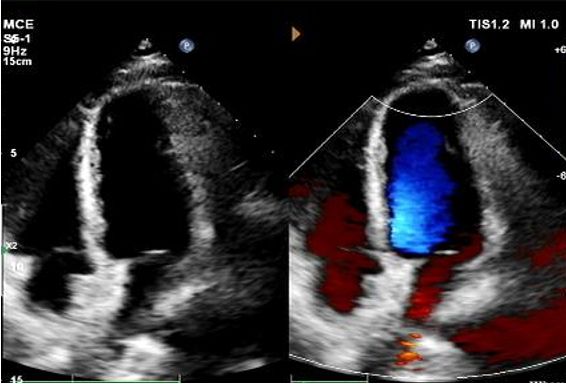

Dias 1 a 9 meses:

Nenhum desvio residual observado.

Redução gradual da ecogenicidade do dispositivo.